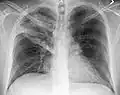

Left upper lobe pneumonia with a small pleural effusion.